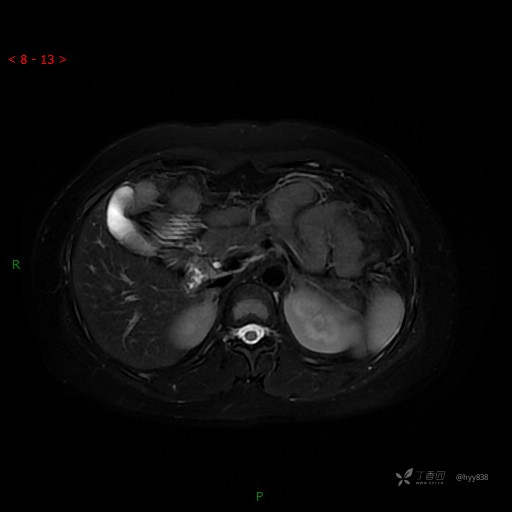

T2WI-fs